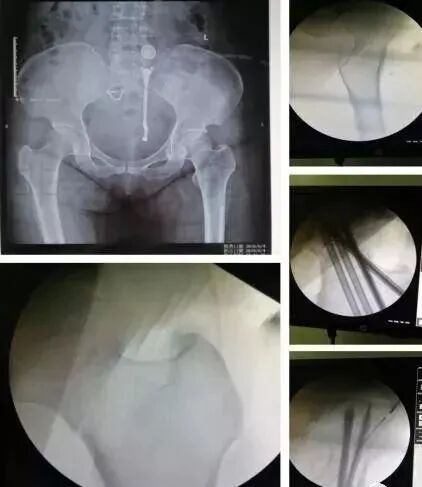

1)股骨近端(股骨头,颈,转子部位)

图片

• <65岁,内固定;>65岁,关节置换

• 患者全身情况稳定,应早期内固定。

• 内固定方式很多,如DHS,pfna等。

2)股骨干骨折

• 可以急诊做,也可以根据情况限期做。

• 多发伤,髓内钉,可能发生脂肪栓塞-肺栓。